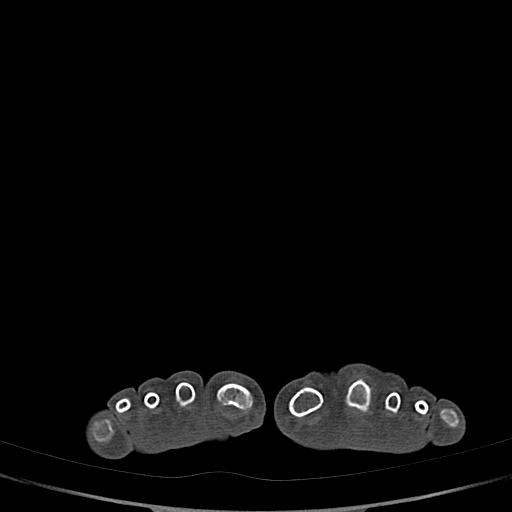

标题: CT13415:M72Y,跖趾关节病变,请会诊 [打印本页]

标题: CT13415:M72Y,跖趾关节病变,请会诊

男72岁左侧跖趾关节肿痛15年,查压痛。

结合平片看看吧。

骨软骨瘤可能性大,请上传x光片.

考虑退行性骨关节病。